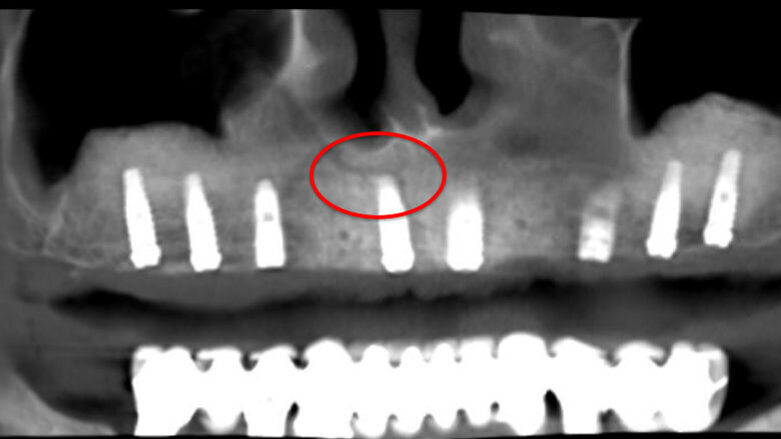

Una paziente di 62 anni, ASA 1 si rivolge alla nostra attenzione per richiedere una riabilitazione dell’arcata mascellare superiore essendo portatrice di protesi mobile totale. L’esame radiologico iniziale evidenzia una marcata atrofia ossea quindi viene progettato l’inserimento di 8 impianti dopo elevazione bilaterale dei seni mascellari al fine di realizzare un a protesi tipo Toronto-Bridge. Trascorsi 8 mesi dai sinus lift e dopo aver accertato la totale guarigione dei siti innestati con una CBCT viene eseguito l’intervento implantare in anestesia locale, sotto profilassi antibiotica, con chiusura dei lembi per prima intenzione e senza eseguire procedure di carico immediato. La paziente viene quindi controllata regolarmente ed a distanza di 7 giorni manifesta una sintomatologia algica localizzata alla zona 1.1 che inizialmente appariva compatibile con il normale decorso post-operatorio. Successivamente a 15 giorni la situazione era nettamente peggiorata trasformandosi in dolore localizzato e persistente con acutizzazioni che la paziente descriveva come “scosse elettriche” o “stilettate”. A questo punto è stata eseguita una nuova analisi della CBCT postoperatoria (Fig. 5) al fine di indagare in maniera più approfondita tale zona, l’analisi delle immagini ha evidenziato la presenza di un CS destro compresso dall’apice dell’impianto in posizione 1.1 (Figg. 6, 7). Tale condizione veniva subito riconosciuta compatibile con la sintomatologia della paziente e si procedeva a rimuovere e sostituire la fixture con una di lunghezza inferiore che non interessasse il decorso del CS (Fig. 8). Veniva quindi prescritta una terapia farmacologica post-operatoria comprensiva di antibiotici, antinfiammatori ed integratori di complessi vitaminici B. La paziente è stata controllata giornalmente manifestando un graduale miglioramento fino a scomparsa della sintomatologia algica a 15 giorni.

Fig. 5 - Panorex Postoperatoria con CS in evidenza.

Fig. 6 - Immagine parassiale raffigurante l’impianto in sede 1.1 che comprime il CS.

Nella moderna chirurgia odontoiatrica la CBCT ha assunto un ruolo predominante nella valutazione pre-operatoria delle riabilitazioni di pazienti parzialmente e totalmente edentuli fornendo immagini affidabili ad alta risoluzione di gran lunga superiori alle precedenti tecnologie bidimensionali. È quindi facilmente capibile come un’attenta valutazione delle immagini pre-operatorie sia necessaria al fine di individuare l’eventuale presenza di un CS: l’immagine migliore per evidenziare il CS è la ricostruzione Panorex (Fig. 5), ricavata dalle immagini assiali, oppure l’immagine coronale (Fig. 3). Qui infatti possiamo evidenziare l’origine del CS dal nervo infraorbitario, la doppia curva a livello dell’apertura piriforme ed il decorso coronale fino all’emergenza nel forame accessorio. Da un punto di vista radiologico tuttavia bisogna ricordare che tutte le ricostruzioni (specialmente quelle con panorex e cross-sections/parassiali) possono portare alla formazione di artefatti quindi il nostro sospetto diagnostico andrà verificato sulle immagini assiali originali ripartendo dal forame infraorbitario e seguendo il percorso fino all’emergenza palatina (se radiologicamente evidente). Gli aspetti chiave da ricercare nelle immagini assiali sono la radiotrasparenza del contenuto del CS circondata da un orletto radiopaco come tipico di un canale infraosseo contenente un fascio vascolo-nervoso.